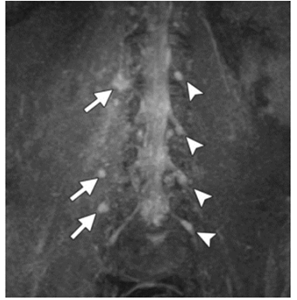

O plexo lombossacral abrange o suporte da pelve óssea, que

protege as raízes nervosas contra alongamento e ruptura

excessivos. Nesse sentido, observe a imagem a seguir.

A imagem em MIP3D TSE coronal STIR mostra